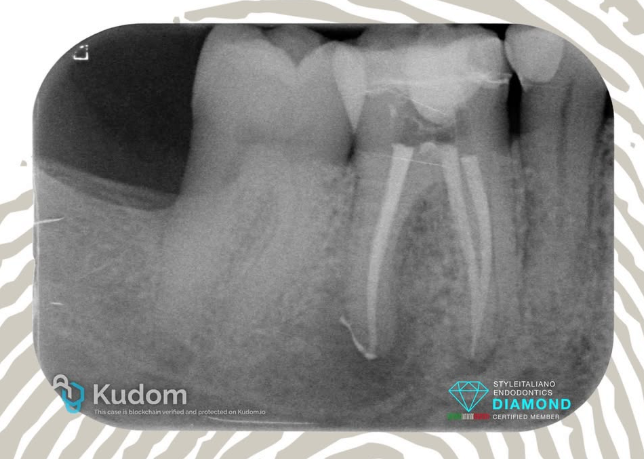

Pulpitis 4.7 with a complex anatomy - 6 years follow-up.

Patient was referred for the treatment of 47 with pulpits few weeks after the cementation of the crown. Challenging anatomy in the mesial root with a double curvature that impede the proper execution of obturation with the Warm Vertical Compaction. The tooth was treated in 2 visits. During the first visit the tooth was shaped, cleaned and dressed. During the second visit the canals were obturated using the Cold Hydraulic Condensation Technique, a single cone with CeraSeal bioceramic sealer.

Review at 1 and 6 years shows the stability of this sealer based technique with a partial resorption of the bioceramic sealer extruded beyond the apex in the distal root.